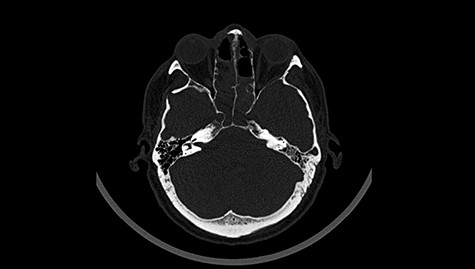

A 49-year-old patient presented after surgical treatment of nasal polyps, with headache and consciousness disorders (behavioral changes, drowsiness and allophenic orientation disorders). Computed tomography (CT) scan showed (Fig. 1) a presence of blood in fluid spaces, widening of the ventricular system (without active hydrocephalus features) and presence of air in the frontal horns of the lateral ventricles and features of cerebral edema. Due to the subarachnoid hemorrhage, an angio-CT and CT scan was performed, showing no vascular malformation. The patient's condition deteriorated with a drop in Glasgow Coma Scale (GCS) to 9, strongly expressed meningeal syndrome and a fever of > 38°C. In the performed cerebrospinal fluid examination a typical picture for bacterial infection, cultures negative. Treatment was implemented in accordance with the neuro-infections algorithm. Clinical and laboratory features of neuroinfections have withdrawn. The neurological condition of the patient improved to GCS 11. Control head CT (Fig. 2) showed enlargement of the ventricular system with cerebrospinal fluid transudation.

Head CT after polypectomy—presence of blood in fluid spaces, widening of the ventricular system, presence of air in the frontal horns of the lateral ventricles, features of cerebral edema. (Department of Neurosurgery Neurotraumatology and Pediatric Surgery own material).

In described case, a head CT scan after polypectomy confirmed the subarachnoid hemorrhage (Fig. 1). In addition, the presence of air in the ventricular system was visible, and presence of defects of the upper left orbital wall and ethmoid on both sides (Fig. 3). In the CT scan sphenoid sinus, frontal and ethmoidal sinuses on both sides and right maxillary sinus airless, filled with blood and soft tissue. The changes also concerned the lateral part of the left maxillary sinus (Fig. 4).